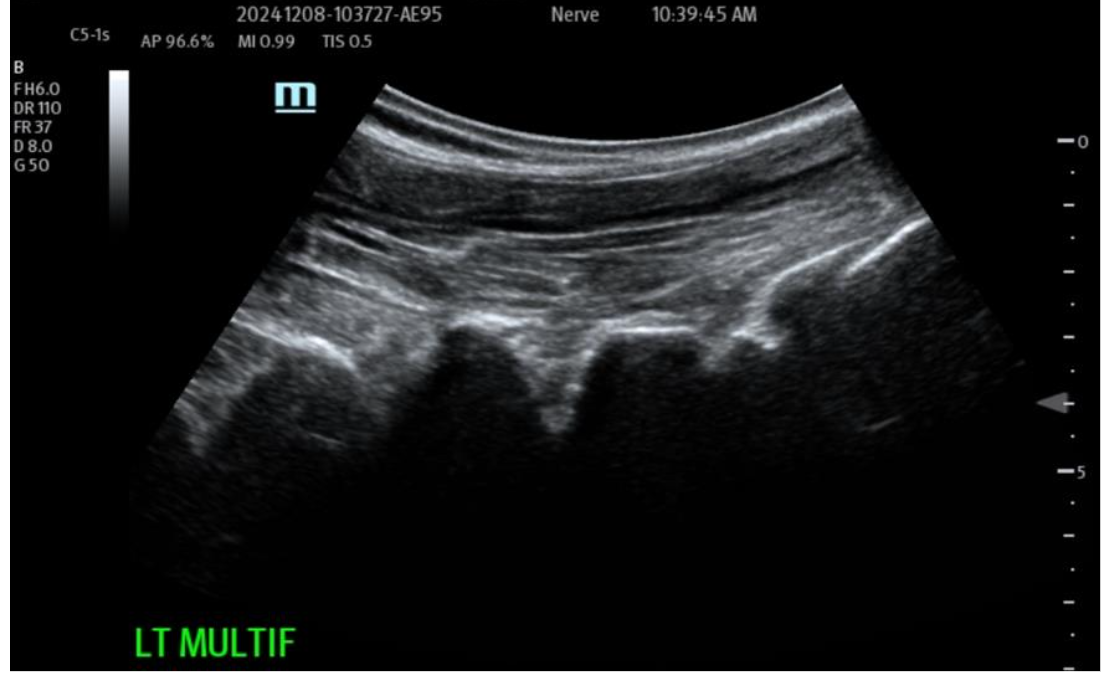

Figure 3: Pre-operative treatment site Multifidus (loss of function dynamically) at L4-5 and above. Multiple targets IM for return of function and architecture. NOTE: Likely most common site that accompanies Lumbar facets pain seen together and is treated.

Muscular/Scar Repair: The ability of the biocellular mixture in the repair of torn, damaged or failed muscular structures is quite remarkable. This is accentuated in light of the difficulties relative to internal muscle repair of damage as seen in trauma or invasive surgery. Often rapid responses are realized, with both avoidance of scarring OR the reduction of scarring present has been well shown in many clinical cases. With enhanced vascularity and perfusion within the damaged muscular tissues, limited or less scar formations are important advantages. Some Providers define a ”toxic” inflammatory reactions as those that lead to tissue scarring. This is seen in unstable or excessive inflammatory scar reactions which are not desirable. Avoidance of excesses or hypertrophic scarring is a clear advantage to wound healing and long-term outcomes for patients. Nanofat stem/stromal elements are capable of forming smooth, skeletal and cardiac muscle. Biocellular therapy helps a more stable and less inflammatory environment. This coupled with the existing damaged muscle can lead to excellent reformation and return to function. This modality is becoming very common to include direct intramuscular guided placements to improve the internal architecture (sonographic echotexture restoration), and confirmed with dynamic testing of the musculature during the ultrasound from diagnostic and treatment when tracked in follow up examinations.